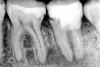

Panttera Опубликовано 20 августа, 2012 Поделиться Опубликовано 20 августа, 2012 Здравствуйте, уважаемые врачиПодскажите, пожалуйста, по снимкам нижние 2 зуба и под ними как будто воспаление, ничего не болит ничего не беспокоит, зубы хорошо запломбированы, как лечить? нужно ли лечить?Очень не хочется удалятьСпасибо заранее за отклики Ссылка на комментарий

shishok Опубликовано 20 августа, 2012 Поделиться Опубликовано 20 августа, 2012 На шестом на задней поверхности кариес под пломбой,седьмой вообще не оптимистичен-пустые каналы и воспаление на корнях(как минимум- перелечивать,а,возможно,и удалить его придётся). Ссылка на комментарий

DokDent Опубликовано 20 августа, 2012 Поделиться Опубликовано 20 августа, 2012 3.6 -лечением кариеса не обойдётесь.Необходимо будет лечение каналов. Ссылка на комментарий